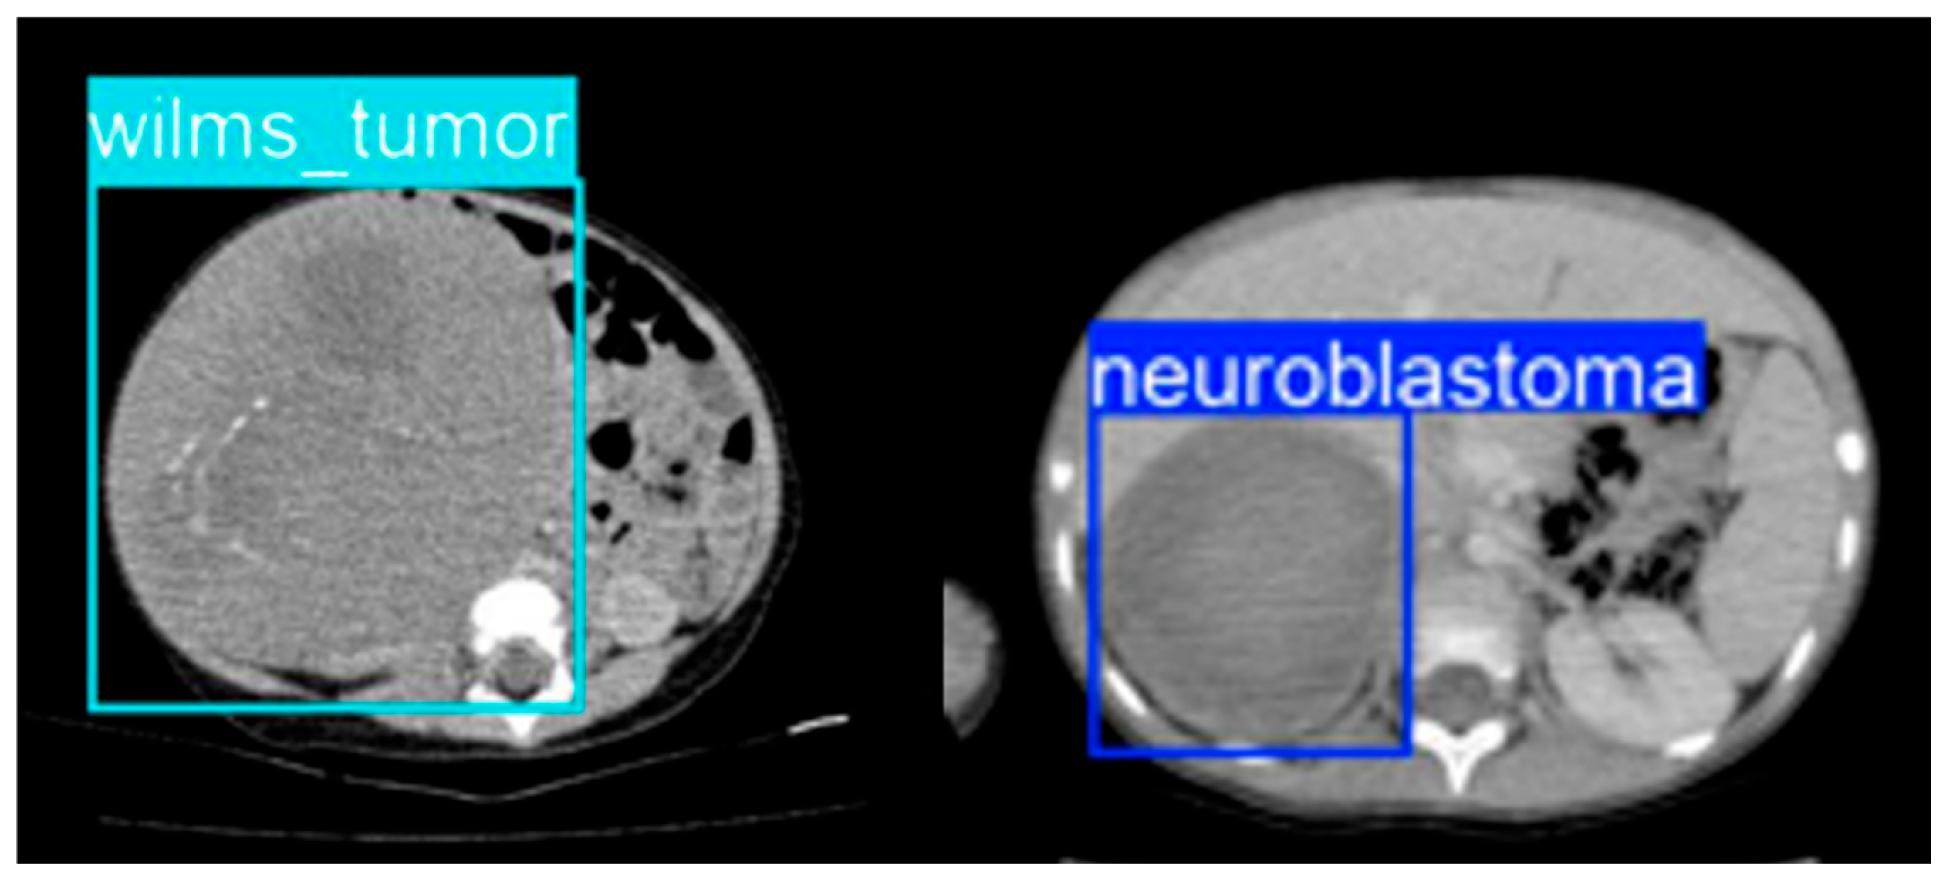

On the held-out test set, lesion-level performance remained strong. Overall test-set precision was 0.954, with a recall of 0.951, an mAP@0.5 of 0.977, and an mAP@0.5:0.95 of 0.732. For neuroblastoma, the model achieved a precision of 0.948, a recall of 0.926, an mAP@0.5 of 0.971, and an mAP@0.5:0.95 of 0.734. For Wilms tumor, the corresponding values were a precision of 0.960, a recall of 0.976, an mAP@0.5 of 0.983, and an mAP@0.5:0.95 of 0.730. Thus, lesion localization performance was high for both tumor classes, without a substantial performance drop in either category. Sample detection results can be seen in Figure 3.

Figure 3. Sample detection results.